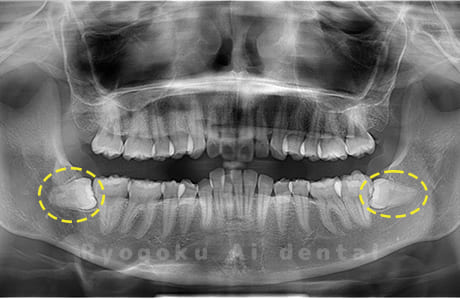

斜めに生えている親知らず

親知らずが斜めに生えて隣の歯にぶつかって圧迫してしまうタイプです。

このタイプが最も多いです。このタイプは虫歯になりやすいだけでなく、隣の歯を圧迫し、咬み合わせや歯並びに影響が出る場合もあるので抜歯をおすすめします。